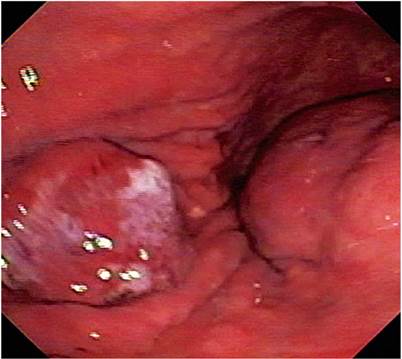

The 74-year-old patient was admitted after three days of hematemesis and melena. Upper digestive endoscopy found an elevated, 20 mm in diameter lesion with an ulcerated center in the middle of the corpus towards the anterior wall as well as a 60 mm subepithelial lesion in the antrum. The initial endoscopic diagnosis a type 0-IIa elevated gastric lesion and a type 0-IIc subepithelial lesion (GIST?) (Figure 1). Multiple biopsies of the lesions were taken.

Figure 1 The image shows both lesions. The one on the left corresponds to early gastric cancer and the one on the right corresponds to GIST.